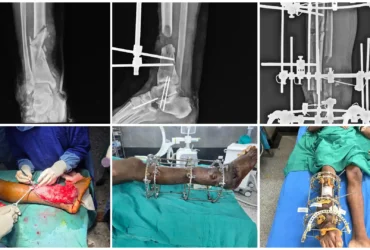

●DEFORMITY CORRECTION

●COMPLICATED FRACTURES

●FAILED FRACTURES

●TRAUMA CARE WITH DEEP ACCURANCY

We Provide Orthopedic Service by Experience Doctors

We has a dedicated multidisciplinary team that cares for and surgically repairs acute fractures for patients of all ages. We offer expertise in fractures of the hip, arm, leg, hand, foot and ankle.